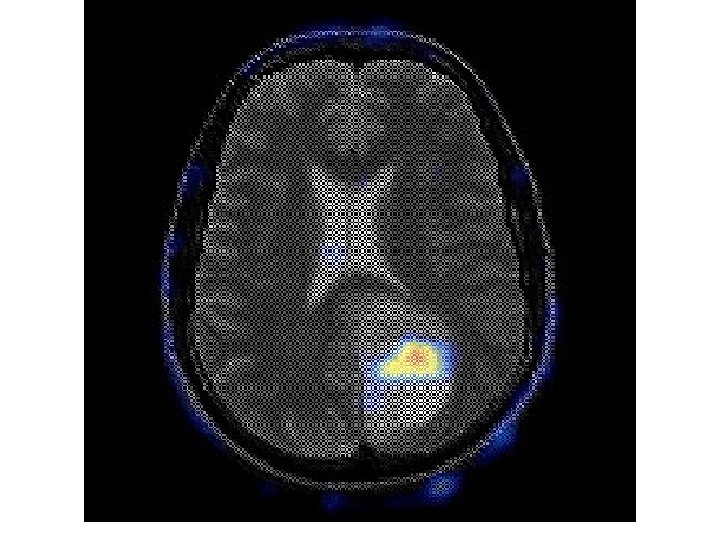

PET Scan & SPECT Scan • PET = Positron Emission Tomography • Single Photon Emission Computed Tomography • X-rays/MRI with Radioisotopes 56

57

• PET Scan showing diffuse spread of prostate cancer to bone. PET has the advantage over traditional bone scanning in its ability to differentiate active from dormant disease. 59

PET Scan & SPECT Scan • PET = Positron Emission Tomography • Single Photon Emission Computed Tomography 76

Prostate cancer metastasized in bones 78

PET NUCLEAR MED + CT or MRI- co-registration 79